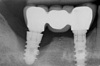

IMPLANTOLOGIE : LA PÉRI-IMPLANTITE, COMPLICATION CLASSIQUE À TRAITER SANS TARDER